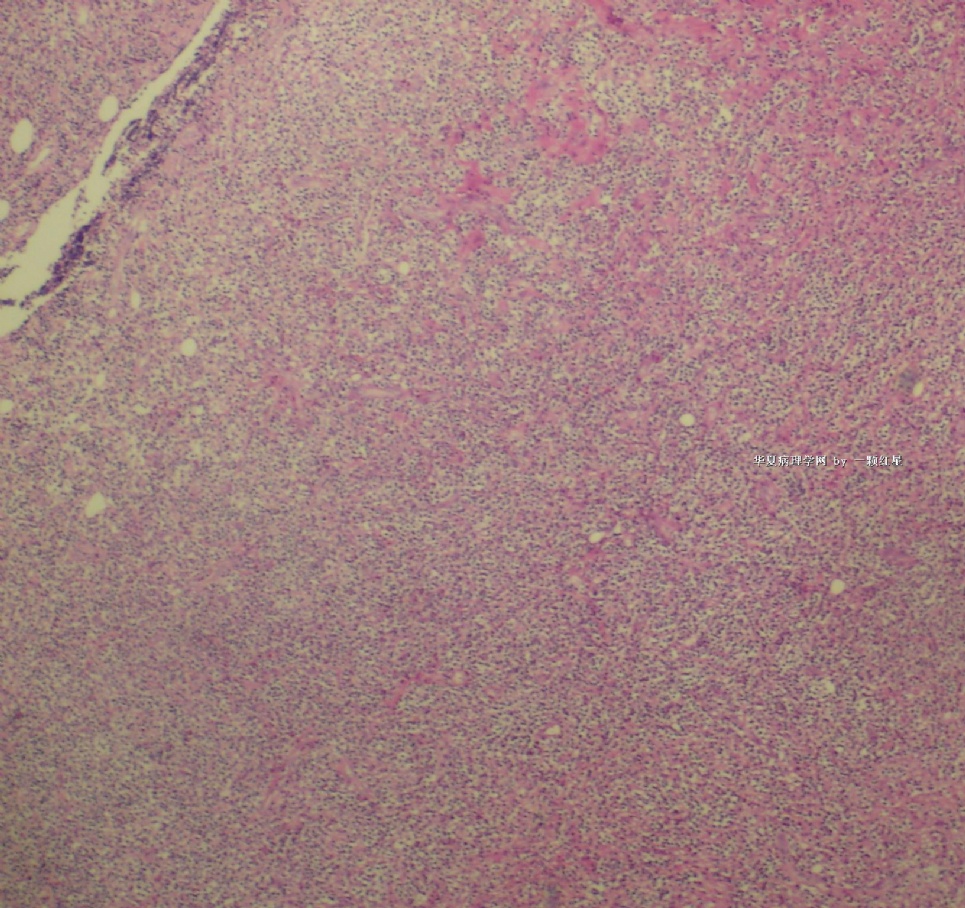

标本名称:  左前臂数个大小不等的皮下肿物。

既往有非何杰金淋巴瘤(滤泡性淋巴瘤)病史22个月。

• 左前臂数个大小不等的皮下肿物     淋巴瘤?图3

图3

病例不错。细胞胞浆透亮,间质血管丰富,图片不是很清晰,似乎有嗜酸粒细胞?

恶性,首先考虑T-NHL。IHC证实。

既往有NHL病史,图片不太清晰,细胞弥漫,胞浆透亮,首先考虑T细胞淋巴瘤。